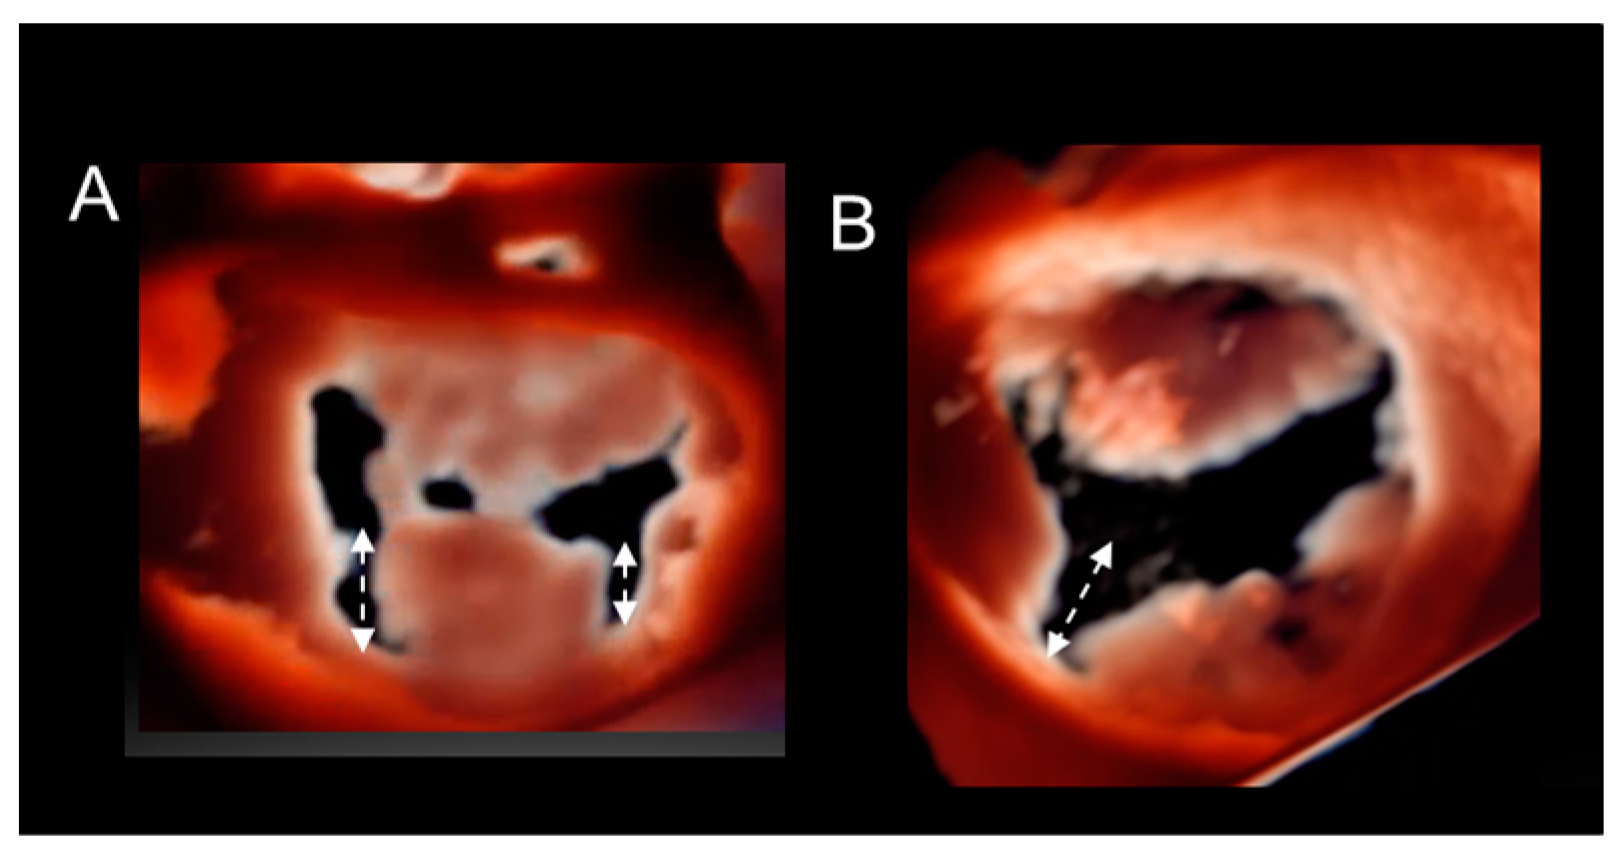

Cleft and Cleft-like Indentations

Different Shapes of P2 Prolapse, Partial Prolapse, and Commissural Prolapse